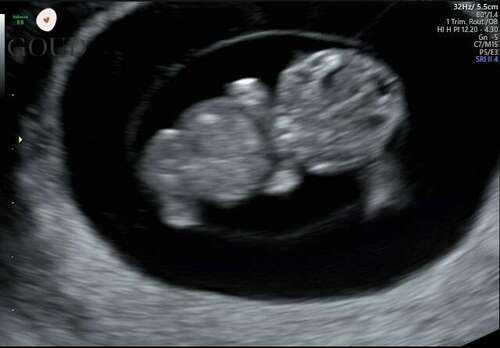

Deze was rond 8+4. Vroeger dan de vorige foto maar scherper beeld door ander echo apparaat!